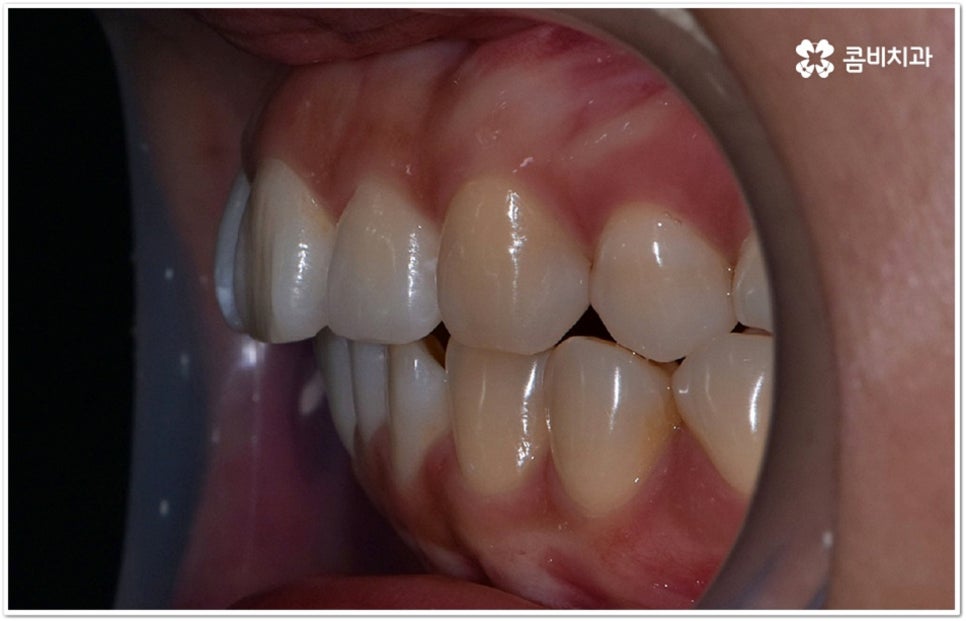

사실 치아가 많이 겹쳐서 삐뚤빼뚤하면 보기에도 좋지 않고 사이사이에 음식물 찌꺼기가 끼어서 충치 같은 구강 질환도 더 자주 발생할 수 있기 때문에 환자분들의 입장에서도 교정 치료를 고려하시는 경우가 많지만, 아주 살짝 덧니가 있을 때는 교정에 대해서 별로 심각하게 생각하지 않으실 수도 있는데요. 이런 덧니는 사람에 따라 오히려 매력 포인트가 될 수도 있기 때문에 스스로 느끼기에 문제가 아니라고 생각한다면 반드시 교정 치료를 해야 하는 것은 아니지만, 만약 입을 벌렸을때 잘 보이는 앞니, 송곳니 등이 덧니라서 웃거나 말을 할 때 신경이 쓰이거나 자기도 모르게 손으로 가리는 습관이 들 정도로 자신감이 떨어진 경우라면 한 번쯤 고려해 보셔도 좋을 거예요. 특히 위아래 맞물림에 문제가 없고 구조적인 부분과 관련된 원인이 크지 않다면 덧니부분교정 을 통해서 보다 빠르고 간편하게 개선이 가능한 케이스도 있기 때문에 꼼꼼한 검진을 통해 자신의 상황이 어떤지부터 알아보시길 권유드리고 있습니다.

덧니의 원인에는 여러 가지가 있는데 대표적으로는 유치가 너무 일찍 빠져서 영구치가 제대로 자리를 잡지 못했거나 턱뼈의 크기와 치아 크기가 조화를 이루지 못하는 경우 등 공간이 부족한 상황을 생각해 볼 수 있어요. 덧니는 주로 송곳니가 가장 흔하나, 치열이 공간이 부족할 경우 이론적으로는 어떤 치아라도 덧니가 될 수 있어요. 이때 원인과 정도를 꼼꼼하게 파악하여 만약 해당 부위만 부분 교정이 가능하다면 덧니부분교정 치료를 할 수 있는데요. 덧니부분교정 을 이용하면 원하는 부위에만 브라켓을 부착하여 치아 이동을 시키기 때문에 전체 교정에 비해서 간편하며 치료 기간도 6~8개월 정도로 줄어들고 통증도 많이 감소될 수 있습니다. 비용적인 부담도 덜하며 (삐뚤어진 정도나 상태에 따라 다르겠지만) 보통 덧니부분교정 의 경우 비발치 과정으로 진행되기 때문에 환자분들의 입장에서는 덧니부분교정 을 많이 선호하시는 편이라고 할 수 있어요. 상황에 따라 미니스크류, 치간삭제, 악궁확장장치 등 환자에게 맞는 비발치 방법을 이용하여 도움 받을 수 있습니다.

하지만 모두에게 덧니부분교정 을 적용할 수 있는 것은 아니므로 먼저 3D CT와 같은 정밀 검사 장비를 통해서 턱의 구조적 특성 및 치열과 교합 등 구강 내부 상황에 대해 세세하게 검진을 하고 충분한 상담을 통해 각자에게 적합한 계획을 세운 다음 무리하지 않게 치료를 진행할 필요가 있어요. 만약 부분 교정을 진행할 수 없다고 해도 교정 장치를 이용하여 기간이나 통증 부분의 부담을 덜 수 있으니 너무 실망하실 필요는 없을 거예요.